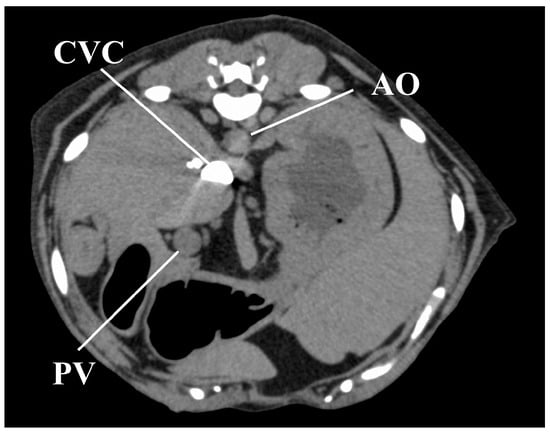

With regard to time-based parameters, in four dogs under the sedation protocol, CVC enhancement occurred earlier than AO enhancement, with a strong peak of CVC enhancement (Figure 5). We noted that in one dog in the sedation protocol, an early strong CVC enhancement was not observed, with a CVC-EA value of 50 s, CVC-EP value of 74 s, and a peak enhancement value of 154 HU (Table 1). Not only was the contrast enhancement earlier with the sedation than the anesthesia protocol (namely, CVC-EA and CVC-EP) in this animal, but also the peak enhancement value of CVC (CVC-EP) reached a maximum under the sedation protocol. All dogs fully recovered from anesthesia and sedation.

With sedation, except in one dog, contrast enhancement of the CVC appeared earlier than the effect in the AO. Moreover, contrast enhancement values of the CVC were the highest among all measured contrast enhancement values, with this state persisting for at least 40 s after the administration of contrast medium. This finding is indicative of a sedation-induced bradycardia and a weakened cardiac output; therefore, the contrast medium may have stagnated in the CVC without entering the pulmonary circulation. In humans, this characteristic effect is known as the “inferior vena cava level contrast” or “dependent pooling sign” and is observed clinically in patients who are in shock due to cardiac arrest, cardiac tamponade, or myocardial infarction [28,29,30]. This effect, in humans, results from the contrast medium permeating into the CVC from the right atrium due to reduced cardiac output and blood pressure. However, all dogs in our study did not exhibit hypotension under sedation. Hence, the CVC effect observed was likely due to a reduced cardiac output secondary to both, bradycardia and an increase in afterload.

Figure 5. Image obtained 11 s after injection of the contrast medium in one representative dog under the sedation protocol, showing a strong CVC enhancement, with no contrast in the AO and PV. AO, aorta; CVC, caudal vena cava; PV, portal vein.